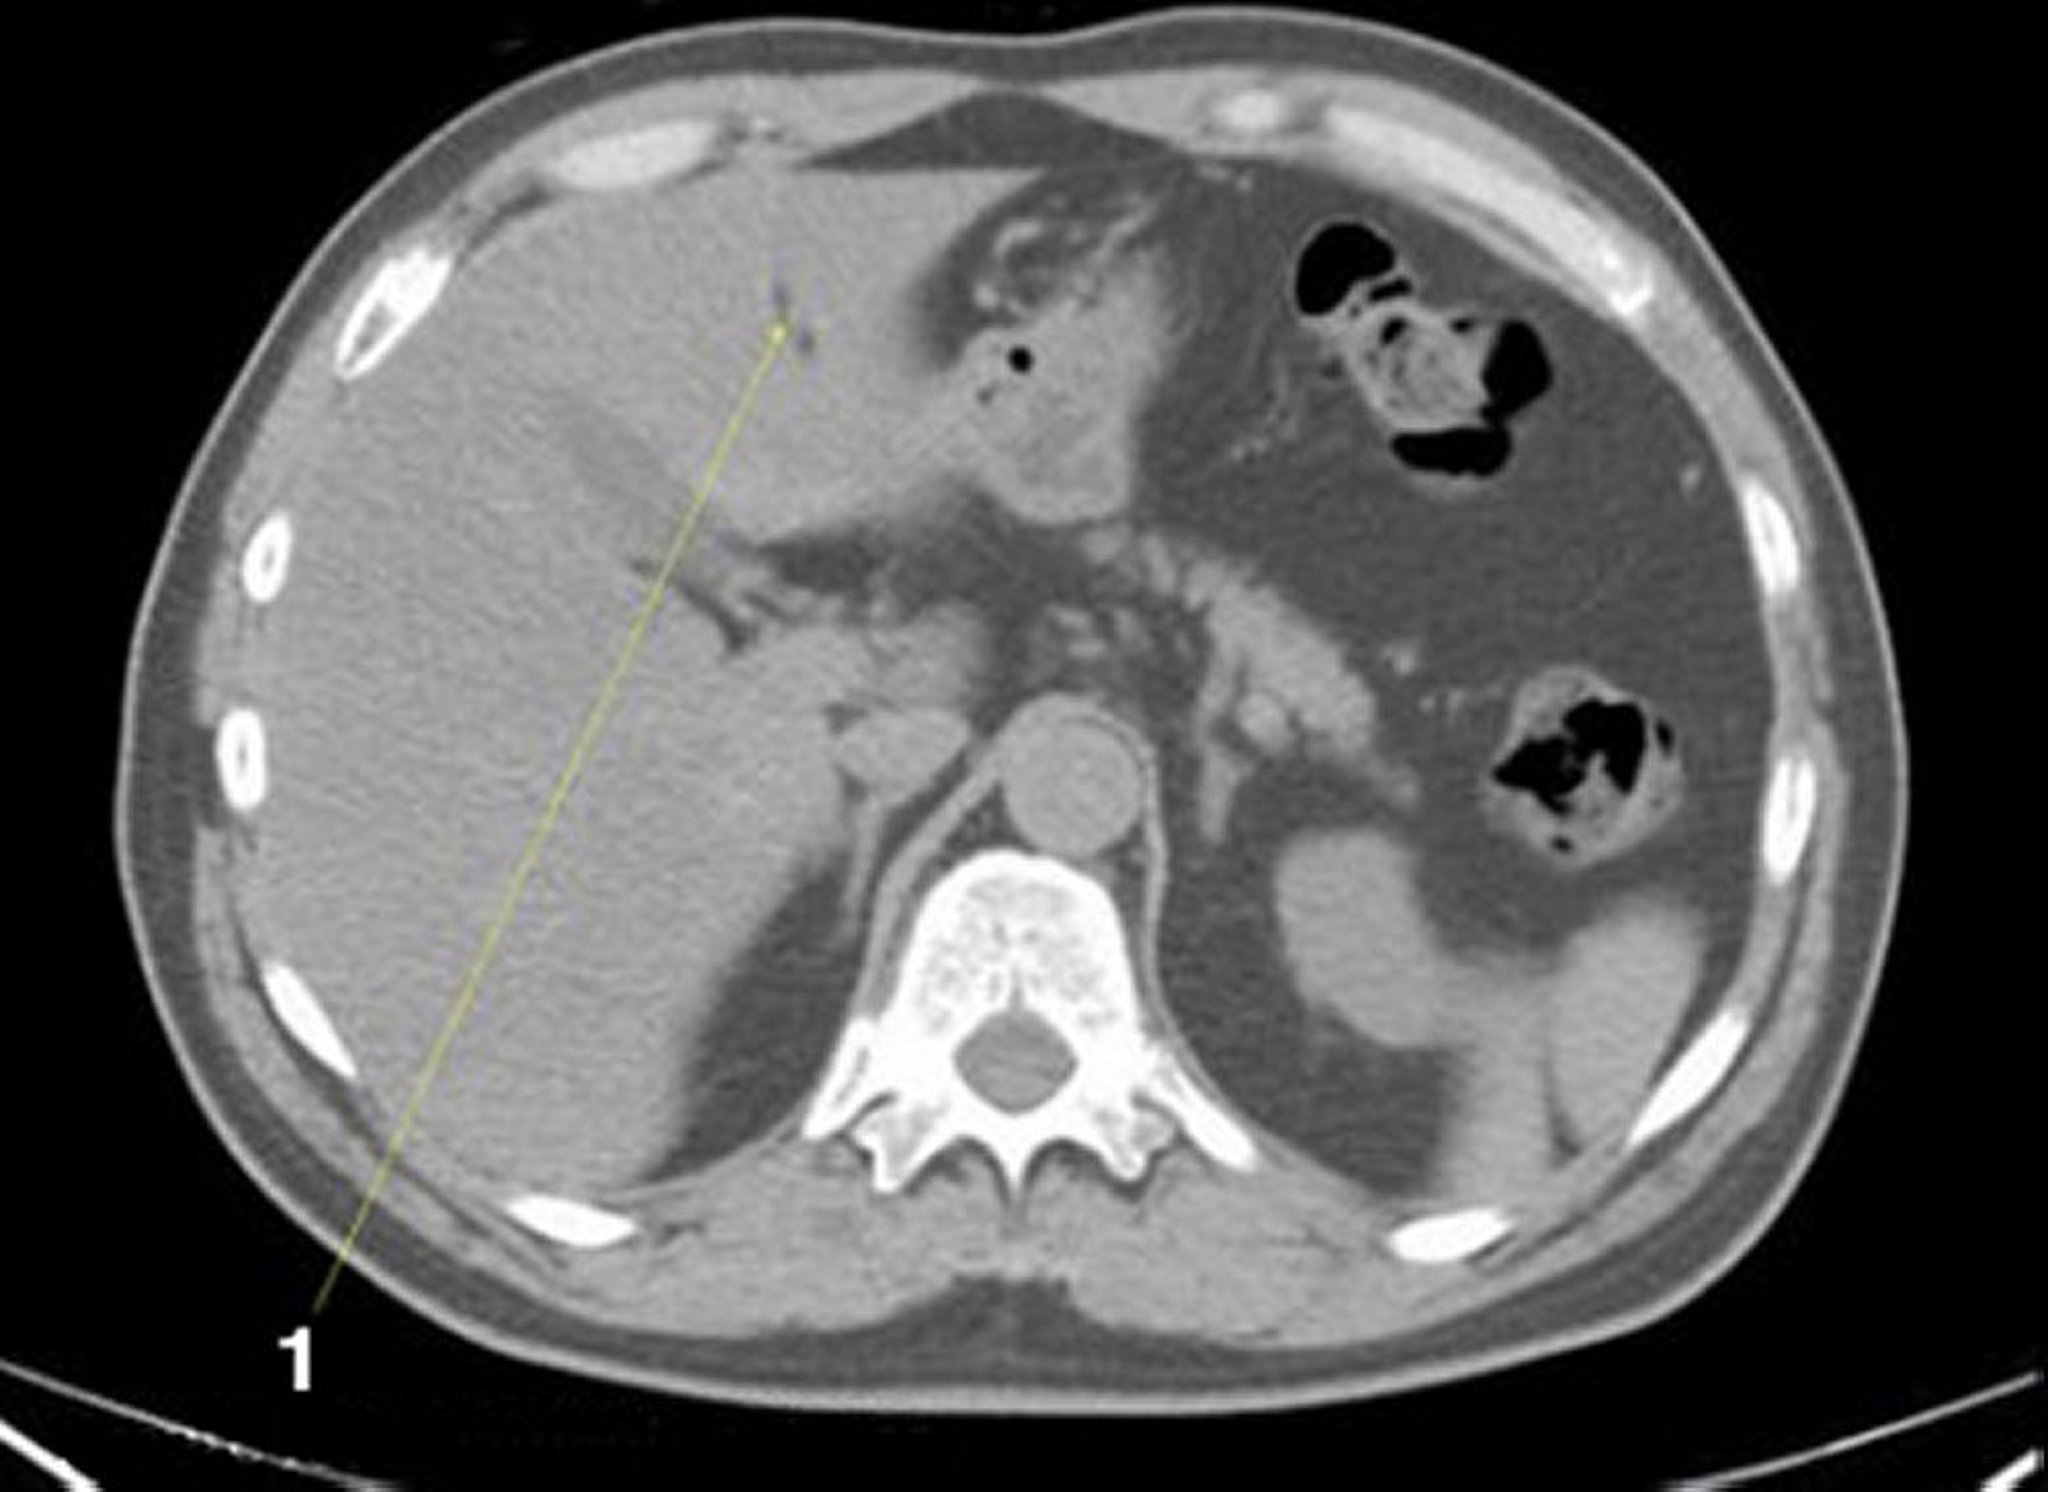

TDM sans contraste de l'abdomen et du bassin montrant une anatomie normale (diapositive 5)

1 = fissure du ligamentum teres (ligament rond).